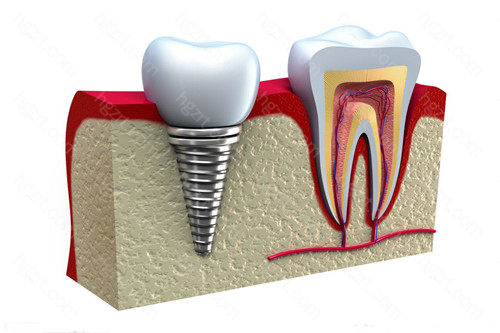

种植牙是一项很考验医生技术的手术,所以选对牙科医院就比较重要,那么在茂名种植牙医院哪个好呢?这几家种牙技术好的牙科你可以了解下。1...

准备做种植牙的患者一定都听说过登腾种植体、奥齿泰种植体、诺贝尔种植体、iti种植体……这些耳熟能详的种植体品牌都拥有众多的临床使用病...